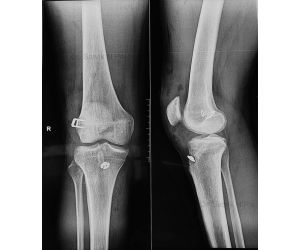

What if Quadriceps Alignment was variable?

Dr. Simon Talbot

Welcome to the very first video in my series on Quadriceps Alignment. These will be very short videos, but it looks like there might be quite a lot...